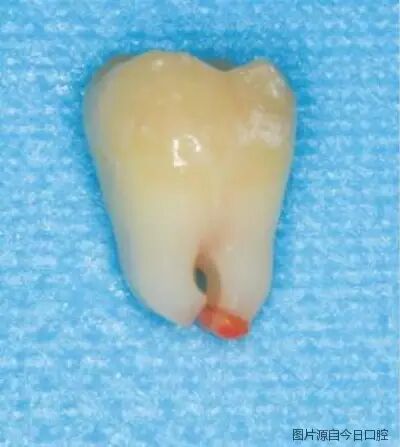

图1 年轻恒牙根尖组织

因此,未发育完全的年轻恒牙根尖孔粗大,根尖组织(图1)中干细胞丰富且活力较强,还可以从周围组织中获得丰富的血液供应,被认为是牙髓坏死和经过牙髓治疗后的年轻恒牙牙根得以继续发育的主要种子细胞。因此,牙髓血运重建和根尖诱导成形术都要求尽可能保守地处理患牙根管,仅使用药物冲洗根管,尽量少或者不探查根管及机械预备,保留残留牙髓和根尖,以保存牙髓干细胞和根尖干细胞。